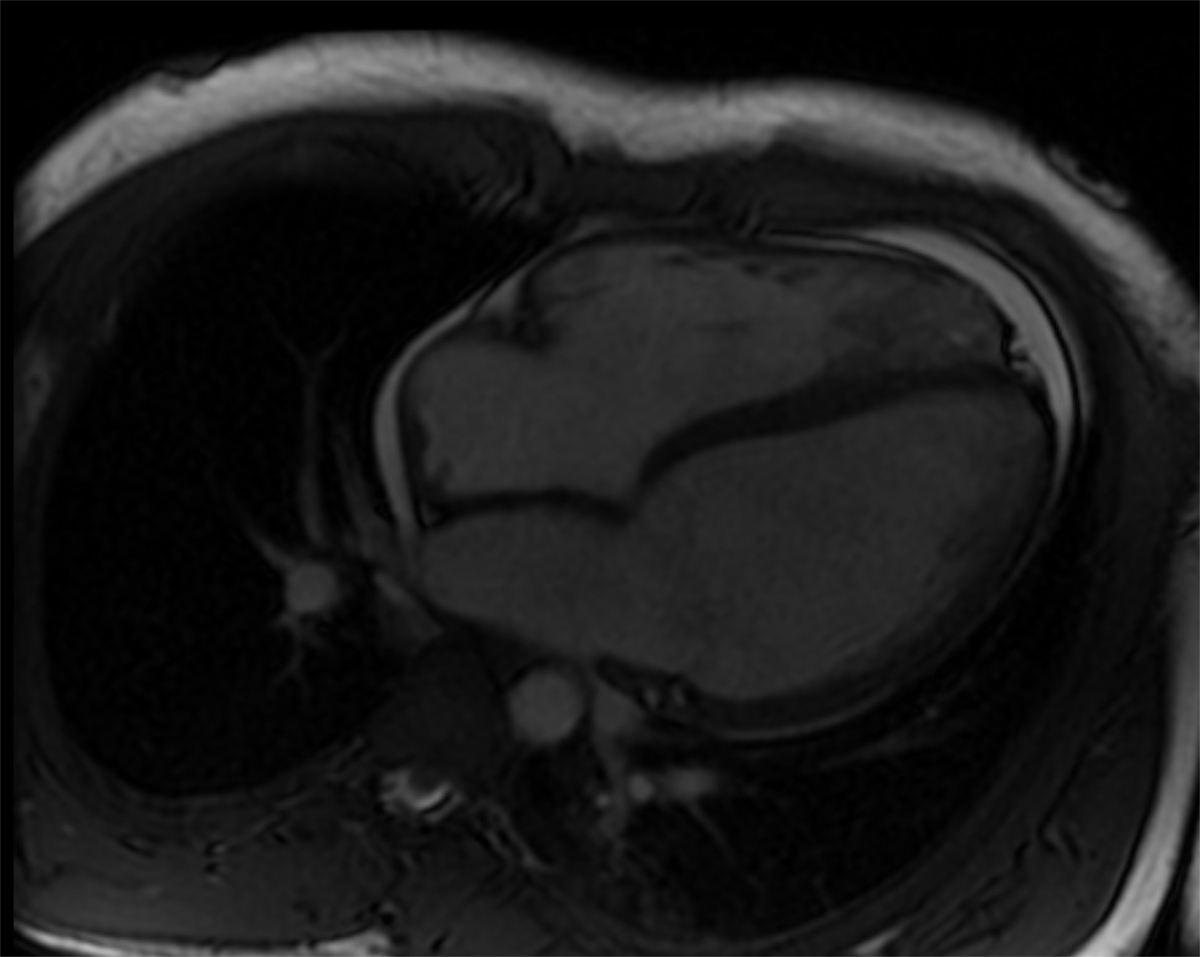

Four days after admission, the patient underwent an extensive cardiovascular MRI examination in a 1.5 T scanner for assessment of ventricular function and myocardial tissue characterisation. Both ventricles were dilated, and ejection fractions were markedly reduced (left ventricular ejection fraction 31%, right ventricular ejection fraction 42%). There was a pericardial effusion (fig. 3). High-resolution 3D steady-state free precession (SSFP) sequence did not reveal coronary abnormalities. No myocardial oedema or myocardial contrast enhancement were detected using a short-axis stack of fat-saturated T2 images and late-gadolinium enhancement images acquired with an inversion recovery gradient echo pulse sequence. However, T1 and T2 mapping revealed prolonged relaxation times of 1100 ms and 62 ms in comparison with normal values [12–14], respectively.

Figure 3 Four-chamber view of the magnetic resonance imaging examination in a 1.5 T scanner. Both ventricles are dilated, and ejection fractions are markedly reduced (left ventricular ejection fraction 31%, right ventricular ejection fraction 42%). There was a pericardial effusion.

Cardiovascular MRI plays an important role in evaluation of COVID-19-related cardiac involvement including coronary artery alterations, ventricular impairment, late-gadolinium enhancement, and myocardial tissue and pericardial abnormalities [28]. Given the wide range of potential COVID-19-associated cardiac pathologies, it is important to include T1- and T2-mapping sequences in the cardiac MRI protocol to detect subtle myocardial alterations that could be missed otherwise. Our findings of prolonged T1 and T2 relaxation times are in line with the current literature [29, 30]. T1 and T2 mapping abnormalities seem to be frequent findings in COVID-associated myocarditis [30]. Mapping techniques have recently been added to the consensus recommendations (Lake Louise criteria) for improved CMR diagnosis of myocardial inflammation [31].

T1 and T2 mapping as tools for detecting diffuse myocardial fibrosis and oedema may act as imaging biomarkers in COVID-19 myocarditis. The pathological mapping results confirm the cardiac involvement in our patient, in addition to ventricular dilation and impairment, as well as signs of pericarditis.